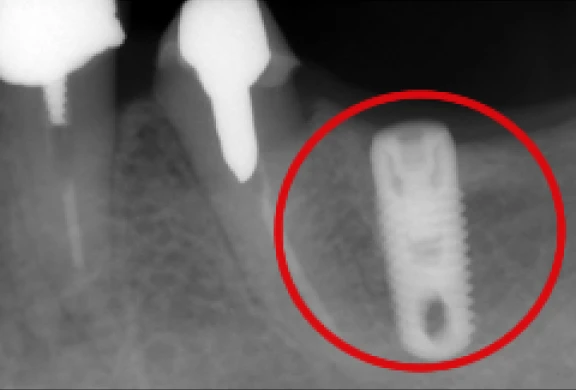

インプラント

自分の歯のような噛み心地を

歯科用CTによる精密診断を行い、お口の中の状態をしっかり把握させていただいた上で、適応のある方は院内にてインプラント治療を行います。

歯を失って再びご自身の歯のような噛み心地をご希望の方は、ご相談いただきたいと思います。

- 歯科用CT(タカラベルモント社BEL-X(ベルクロス))を設置しています。当院で撮影・画像診断を行い、院長自らが手術を行いますので、安心してご相談下さい。

- 当院ではHA(ハイドロキシアパタイト)インプラントを採用しています。

インプラントの埋め込み

-

上部構造の装着

パノラマ

歯間部のインプラント

(上部構造の装着)